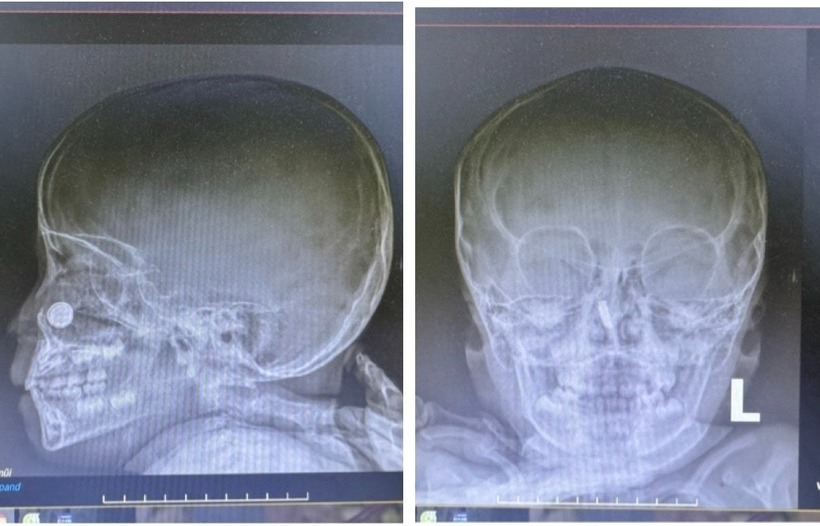

Hình chụp X-quang của bệnh nhi. Ảnh: BVCC.

Sau khi thăm khám và cho bệnh nhi dùng 2 loại kháng sinh phối hợp chống viêm, các bác sỹ Khoa Liên Chuyên khoa đã chỉ định cho bệnh nhi chụp X-quang sọ não mặt thẳng/nghiêng và nhận thấy hình ảnh cản quang vị trí hốc mũi phải.